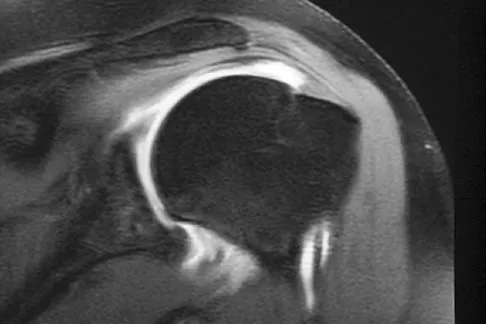

Examination of the shoulder seen in Figure 52 shows atrophy and tenderness of the infraspinous fossa and profound weakness in external rotation. The supraspinous fossa shows normal muscle bulk. What is the most likely cause of this condition?

Explanation